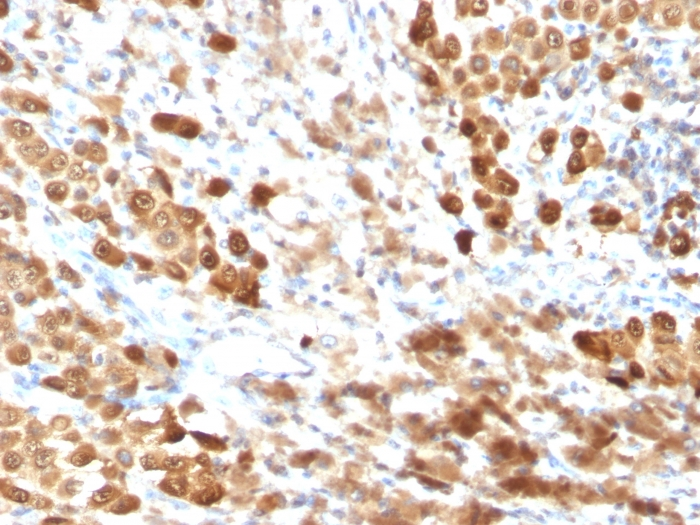

Anti-S100 beta antibody [SPM354] used in IHC (Paraffin sections) (IHC-P). GTX04512

IHC-P analysis of human melanoma tissue using GTX04512 S100 beta antibody [SPM354].